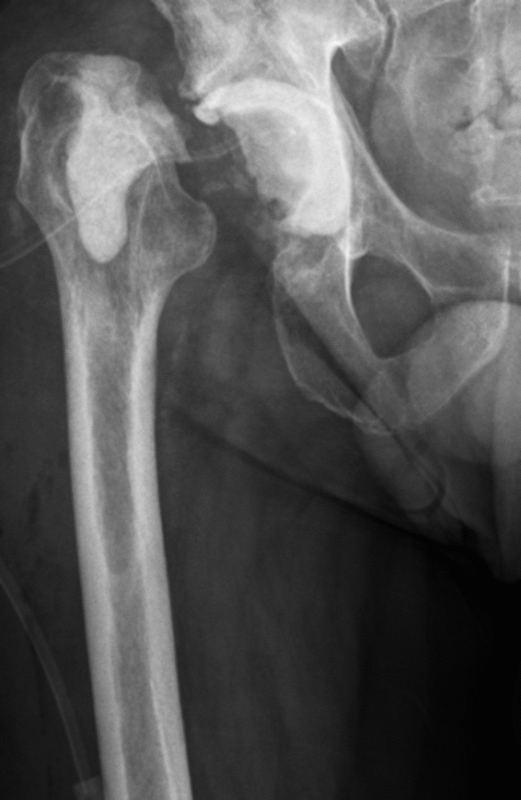

Kurze Vorgeschichte: Herr B., 56 Jahre, hatte Anfang des Jahres 2017 einen Oberflächenersatz des Femurkopfes rechtsseitig (McMinn Prothese, Abb. 1) implantiert bekommen. Mit Schmerzen in der rechten Hüfte erfolgte im Herbst 2017 erstmalig die Vorstellung in domo.

Eine Röntgenaufnahme des Beckens sowie der rechten Hüfte wurde durchgeführt. Hier wurde der Verdacht auf eine Implantatlockerung gestellt und ein CT der rechten Hüfte veranlasst. Hierbei zeigte sich neben den Lockerungszeichen im Bereich der Pfanne und des Implantates im Femur ein Verhalt zwischen Gluteus medius und maximus. Die Hüfte rechtsseitig wurde punktiert und ein multisensibler E. coli festgestellt. Es erfolgte die Planung zur stationären Aufnahme und Revision der rechten Hüfte.

Procedere: Nach der entsprechenden Vorbereitung erfolgte im September der Ausbau der McMinn-Prothese sowie die Resektion des Schenkelhalses, ein Débridement im Bereich des Hüftgelenkes sowie die Einlage eines Spacers (i.S. einer Copal Zementeinlage) in die Hüftpfanne und im Bereich des proximalen Femurschaftes (Girdlestone Situation). Ende November 2017 erfolgte 6 Wochen nach Spacer Implantation (Abbildung 2) eine erneute Wiedervorstellung zur Punktion des Hüftgelenkes als Vorbereitung auf den Prothesenwiedereinbau. Hierbei wurde erneut ein E. coli detektiert und eine antibiogrammgerechte Antibiose mittels Ciprofloxacin 500mg 1-0-1 fortgesetzte. Die Indikation zum Spacerwechsel wurde gestellt. Der Eingriff konnte geplant Anfang Dezember durchgeführt werden.

Ende Dezember erfolgte die erste Punktion des Hüftgelenkes, bei der schließlich kein Keimnachweis erfolgte. Nach 6 weiteren Wochen konnte ebenfalls kein Keim mehr im Hüftgelenk nachgewiesen werden, so dass für März 2018 der Hüft-TEP-Wiedereinbau geplant wurde. Bei der Vorbereitung und Planung (CT Diagnostik) zeigte sich ein relativ großer knöcherner Defekt im Bereich des kranialen Acetabelums, sodass mit einem Burch-Schneider- Ring (Abbildung 3) geplant wurde.